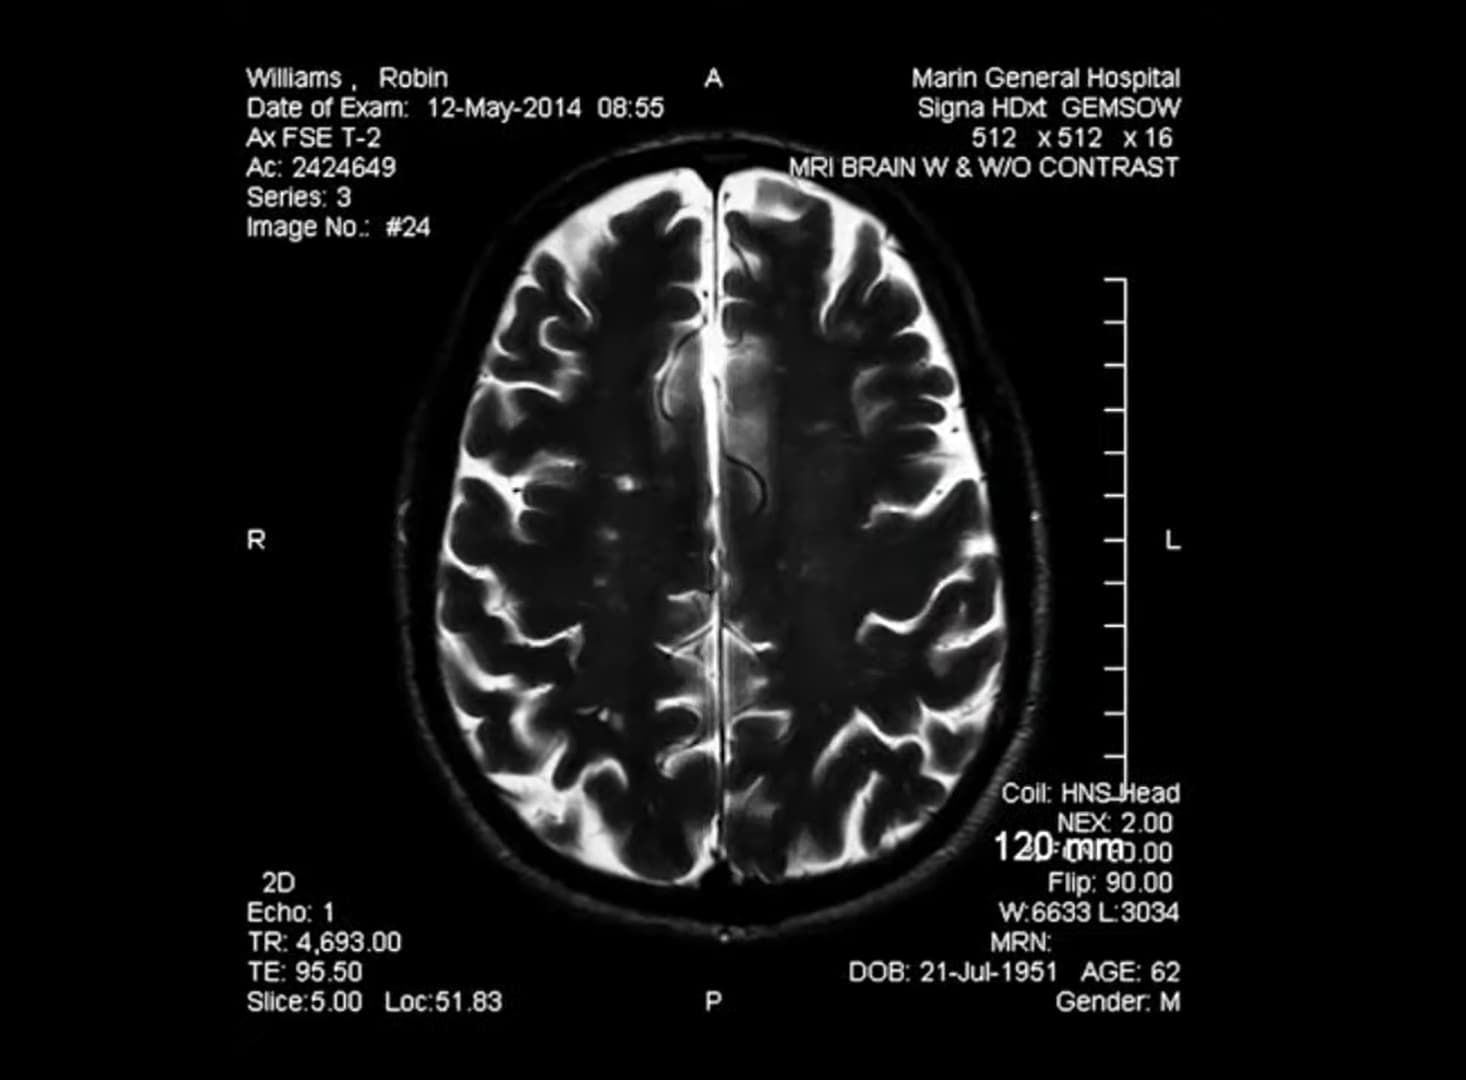

Robin Williams took his own life in August 2014. In October of that year, his widow, Susan Schneider Williams, saw the coroner’s report, which found that the actor had suffered from diffuse Lewy body dementia (LBD), a fatal disease that destroys neurons in the brain and causes such symptoms as paranoia, anxiety, and disruption of sleep patterns. According to the Lewy Body Dementia Association, LBD is “the second most common type of progressive dementia after Alzheimer’s disease.”

Although some in the media had speculated that the actor’s suicide was related to controlled substances, the toxicology report came back clean. That was no surprise to his widow, who was sure the actor had been clean and sober at the time of his passing. Instead, she attributes his behavior to the fact that “he wasn’t in his right mind. Those Lewy bodies were in nearly every region of his brain.”

Williams never received a diagnosis of LBD during his lifetime, even though he visited numerous doctors in an attempt to find answers for his deteriorating condition for more than a year before he passed. His wife believes that if he had received an accurate diagnosis, the actor would have at least been able to find some peace.

2. Robin’s Form Of LBD Was One Of The Most “Devastating,” According To A Doctor

After Susan Schneider Williams was told her husband had suffered from LBD, she asked Bruce Miller, MD, a neurologist and director of the Memory and Aging Center at UC San Francisco, to examine the last two years of Robin Williams’s medical records. Miller says in the documentary:

I realized this was about as devastating a form of Lewy body dementia that I’d ever seen. Almost no part [of Williams’s brain] was left unaffected. It really amazed me that Robin could walk or move at all.

Miller explains that because Williams had never received a diagnosis, he had no idea what was causing his symptoms, which might have led to his despair: “[LBD] becomes progressively irreversible, unstoppable. And always fatal, always fatal. It affects many people, and sadly, one of the outcomes is suicide.”